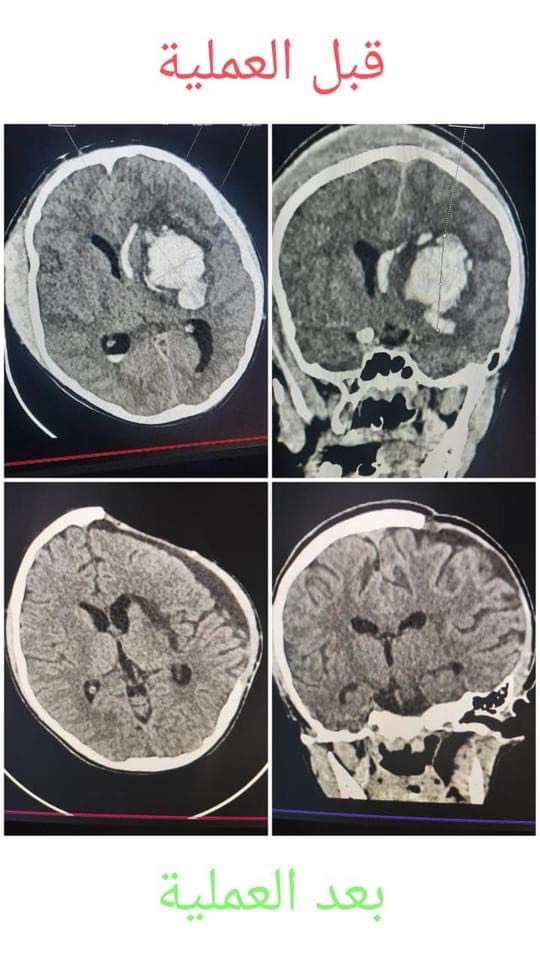

جراحة عاجلة لإنقاذ حياة مريض باسترجاع وترقيع عظام الجمجمة

استطاع فريق طبي بقسم المخ والأعصاب بمستشفي المنصورة التخصصي التابع للأمانة المراكز الطبية المتخصصة بوزارة الصحة من اجراء جراحة عاجلة بالمخ لمريض لانقاذ حياتة باسترجاع وترقيع عظام الجمجمة من البطن

حيث حضر المريض ويبلغ من العمر 15 عاما، إلي المستشفي في حالة غيبوبة عميقة على إثر حدوث نزيف بالمخ مما استدعى دخوله العمليات بصورة عاجلة وقام الفريق الطبي بعدة مراحل أولها تفريغ النزيف من المخ

وذلك كمرحلة أولى ورفع جزء من عظام الجمجمه لتخفيف الضغط الواقع علي المخ والاحتفاظ به في الجدار الأمامي للبطن «Decompressive craniotomy »وبعد ذلك خضع المريض للمتابعه اللصيقة بالعناية المركزة والقسم الداخلي حتي استقرت حالته وبعد ذلك خضع المريض للمرحلة الثانية للجراحة بعمل استرداد لعظام الجمجمه من الجدار الأمامي للبطن وعمل ترقيع للجمجمة «  cranioplasty »والمحافظة على الشكل العام للرأس ، و استقرت حالة المريض علي أن يتم استكمال المتابعه والتأهيل لمزيد من التحسن وضم الفريق  الفريق الطبي كلا من الاستاذ الدكتور رامي عمر السخري، استشاري ورئيس قسم جراحة المخ والأعصاب،